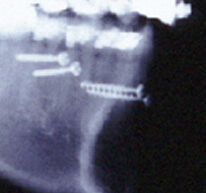

緑のラインは歯槽骨の上縁です。上顎側切歯はかなり低い位置まで骨が下がっています。この歯は保存不可能と診断しました。動揺と排膿もありました。早く矯正治療をしていれば助かりました。さらに状態の悪い下顎右側側切歯も抜歯しました。前歯でも状態の悪い歯、治る見込みのない歯を選択して抜歯します。矯正治療する事で入れ歯やインプラントになる可能性を減らす事ができます。リンガルブラケットを使って矯正治療を開始しました。

レントゲン写真をご覧になって頂くと上顎前歯が下顎前歯を押し出している事がわかります。骨格性反対咬合(受け口)です。下顎前歯が骨から出て行ってしまいそうです。